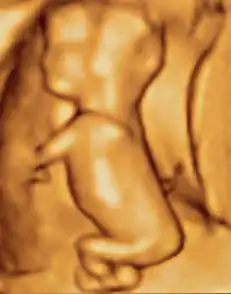

- Ecografia 3D dos movimentos fetais às 12 semanas

Ultrassonografia 3D de um feto de 80-milímetro (3 in) (aproximadamente 14 semanas de idade gestacional)